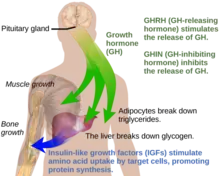

Under normal circumstances in humans, growth hormone (GH) is released in a pulsatile fashion from cells known as somatotrophs in the anterior pituitary gland.[16] These pulses of GH are regulated by cells in the hypothalamus, via the release of growth hormone-releasing hormone (GHRH) into the hypothalamohypophysial system when stimulated by insulin, ghrelin, glucagon, arginine, deep sleep, exercise, fasting, sex hormone release during puberty, and a host of other factors.[16] GH release is inhibited by somatostatin (GHIH), IGF-1, hyperglycemia, and glucocorticoids.[16] Once released, the GH molecules travel through the bloodstream and eventually bind to GH receptors on the surface of cells composing bodily organs and tissues.[16] One major site of action for GH is in the liver, where it stimulates gluconeogenesis and the release of IGF-1 through the JAK-STAT signaling pathway.[16] IGF-1 promotes growth in a variety of tissues throughout the body, especially bone mineralization, and provides negative feedback on GH release.[16] GH results in increased muscle mass, lipolysis, and protein synthesis.[16] Obesity and increased adipose tissue, especially visceral fat, results in reduced GH secretion.[16] There is a natural age-related decline in the GHRH-stimulated release of GH.[16]